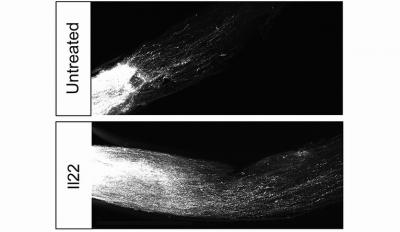

Images of untreated versus Il22 treated optic nerve fibers

Axons extending from the eye (left) to the brain (right) in the optic nerve after the nerve has been crushed. In the control, untreated case (top) very few nerve fibers succeed in growing back. After suppression of Interlukin-22 (Il22) in the retina, many more axons can regenerate from the injury. Image credit: Strittmatter lab, Yale School of Medicine

In a massive screen of 400 mouse genes, Yale School of Medicine researchers have identified 40 genes actively involved in suppression of axon regeneration in central nervous system cells. By editing out one of those genes, they were able to restore axons in ocular nerves of mice damaged by glaucoma.